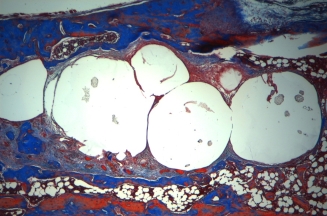

Sa peau a pu être reconstruite principalement avec des greffes de peau autologue cultivée.

Une biopsie de peau de quelques centimètres carrés prélevée sur ce qui lui restait comme peau a permis de produire plus de 113 000 cm2 de greffe de kératinocytes et de fibroblastes. Sébastien Maillard a survécu grâce à la thérapie cellulaire.

objectif : régénérer la peau et accélérer la cicatrisation.